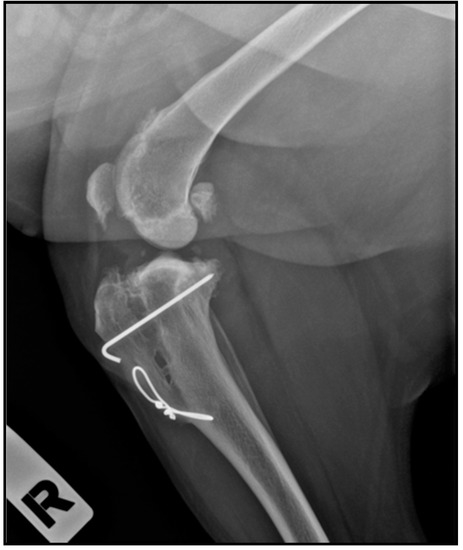

- Valiño-Cultelli, V.; Varela-López, Ó.; González-Cantalapiedra, A. Preliminary Clinical and Radiographic Evaluation of a Novel Resorbable Implant of Polylactic Acid (PLA) for Tibial Tuberosity Advancement (TTA) by Modified Maquet Technique (MMT). Animals 2021, 11, 1271. [Google Scholar] [CrossRef]

- Etchepareborde, S.; Brunel, L.; Bollen, G.; Balligand, M. Preliminary experience of a modified maquet technique for repair of cranial cruciate ligament rupture in dogs. Vet. Comp. Orthop. Traumatol. 2011, 24, 223–227. [Google Scholar] [CrossRef]

- Brunel, L.; Etchepareborde, S.; Barthélémy, N.; Farnir, F.; Balligand, M. Mechanical testing of a new osteotomy design for tibial tuberosity advancement using the modified Maquet technique. Vet. Comp. Orthop. Traumatol. 2013, 26, 47–53. [Google Scholar] [CrossRef] [PubMed] [Green Version]

- Retallack, L.M.; Daye, R.M. A modified Maquet-tibial tuberosity advancement technique for treatment of canine cranial cruciate ligament disease: Short term outcome and complications. Vet. Surg. 2018, 47, 44–51. [Google Scholar] [CrossRef] [PubMed] [Green Version]

- Ness, M.G. The Modified Maquet Procedure (MMP ) in Dogs: Technical Development and Initial Clinical Experience. J. Am. Anim. Hosp. Assoc. 2016, 52, 242–250. [Google Scholar] [CrossRef]